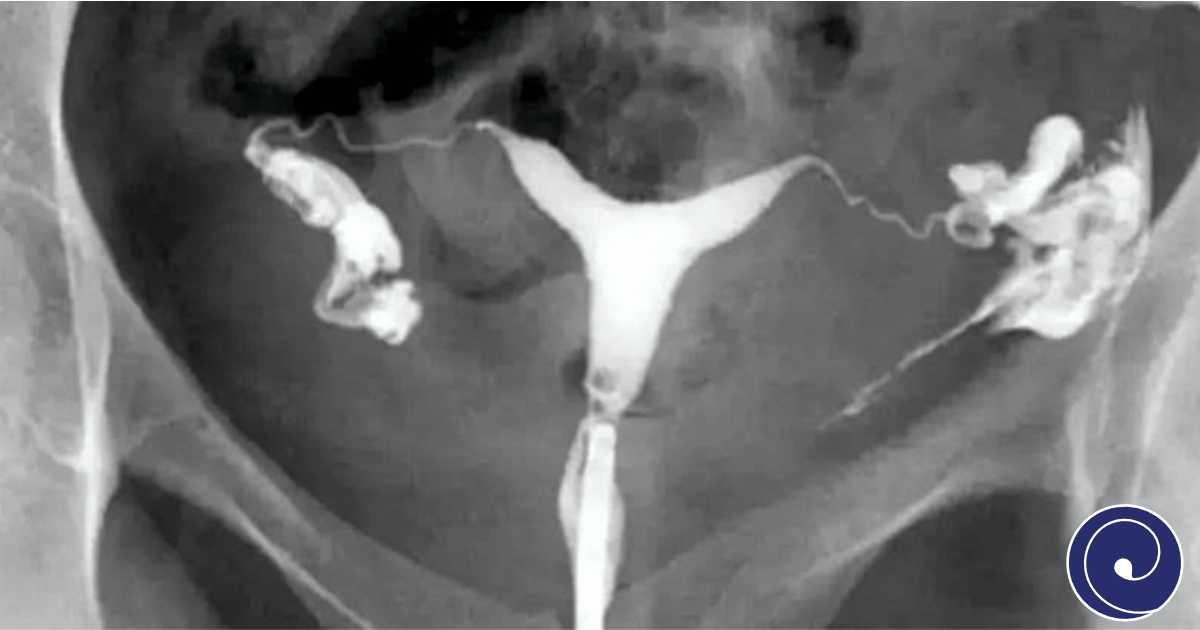

HSG ili histerosalpingografija je radiološki pregled kojim se ispituje prohodnost jajovoda i stanje šupljine maternice. Ovo je jedna od najvažnijih dijagnostičkih metoda u otkrivanju uzroka ženske neplodnosti i bitan korak u planiranju liječenja u Dr Admir Rama IVF Centru.

Histerosalpinografija je specifičan rendgenski pregled koji koristi kontrastno sredstvo da prikaže šupljinu maternice i jajovoda. Na taj način ljekar može vidjeti da li su jajovodi prohodni i da li postoji neka prepreka koja može uzrokovati neplodnost.

• Kroz cerviks se uvodi tanki kateter i ubrizgava kontrastno sredstvo

• Radi se rendgenski snimak koji pokazuje protok kontrasta kroz maternicu i jajovode